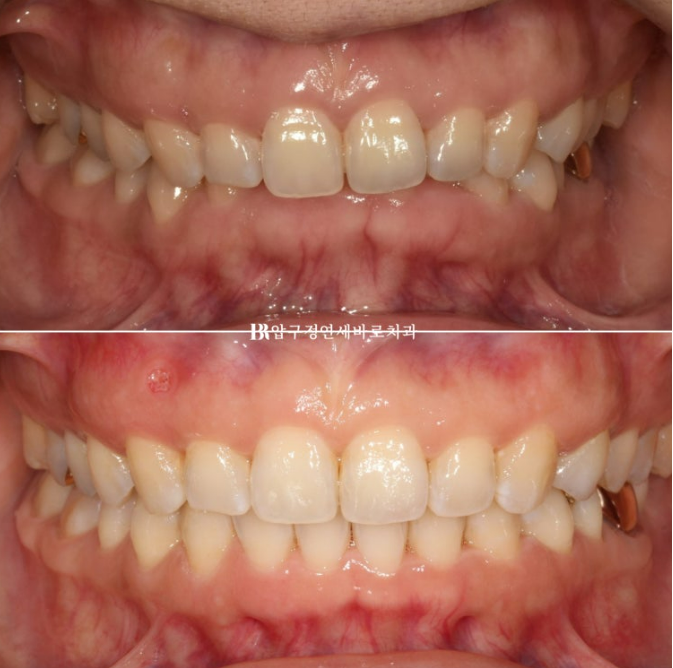

전 후 비교 보겠습니다.

치료기간은 총 11개월이고 재제작은 1회 했습니다.

24.01~24.12

11개월이라는 길지 않은 시간에 교합평면과 치축이 완전히 개선이 되었습니다.

과개교합이 있을 당시 윗니에 가려 숨어있던 아래 앞니 때문에 쏙 들어가있던 아랫입술도 교정 후 볼륨감을 회복하였습니다.